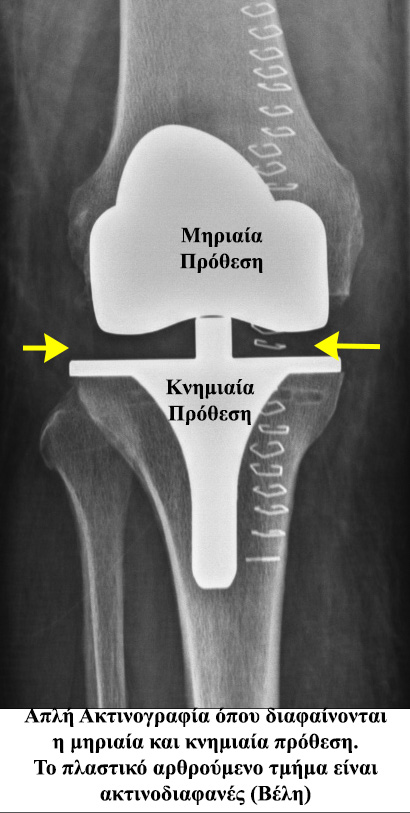

- - Η ολική αρθροπλαστική του γόνατος αποτελεί εμφυτεύσιμο ορθοπαιδικό υλικό το οποίο αντικαθιστά εξ’ ολοκλήρου την άρθρωση του γόνατος.

- - Αποτελείται συνήθως από 2 μεταλλικά μέρη:

- - τη μηριαία πρόθεση και

- - τo κνημιαίο πλατώ

- - και 2 «πλαστικά μέρη:

- - το πολυαιθυλένιο της κνήμης και

- - το πολυαιθυλένιο της επιγονατίδος.